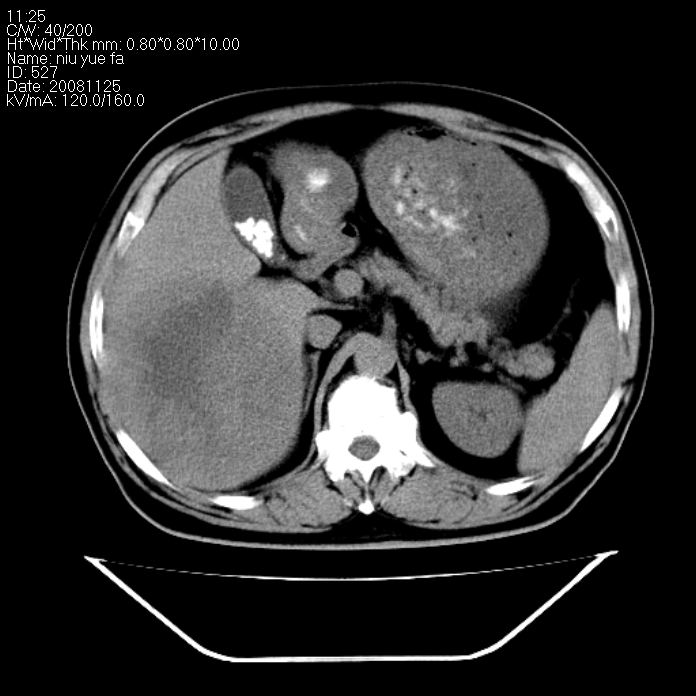

巨块型肝癌,坏死,出血;胆囊结石

1)考虑肝右叶巨块型肝癌并坏死、出血;建议行ct增强扫描检查进一步明确诊断。2)胆囊结石,胆囊炎。

考虑肝右叶巨块型肝癌并坏死、出血;建议行ct增强扫描。胆囊结石。

支持: 1)考虑肝右叶巨块型肝癌并坏死、出血;建议行ct增强扫描检查进一步明确诊断。2)胆囊结石,胆囊炎。

肝右叶巨块型肝癌并坏死、出血;胆囊结石,胆囊炎。